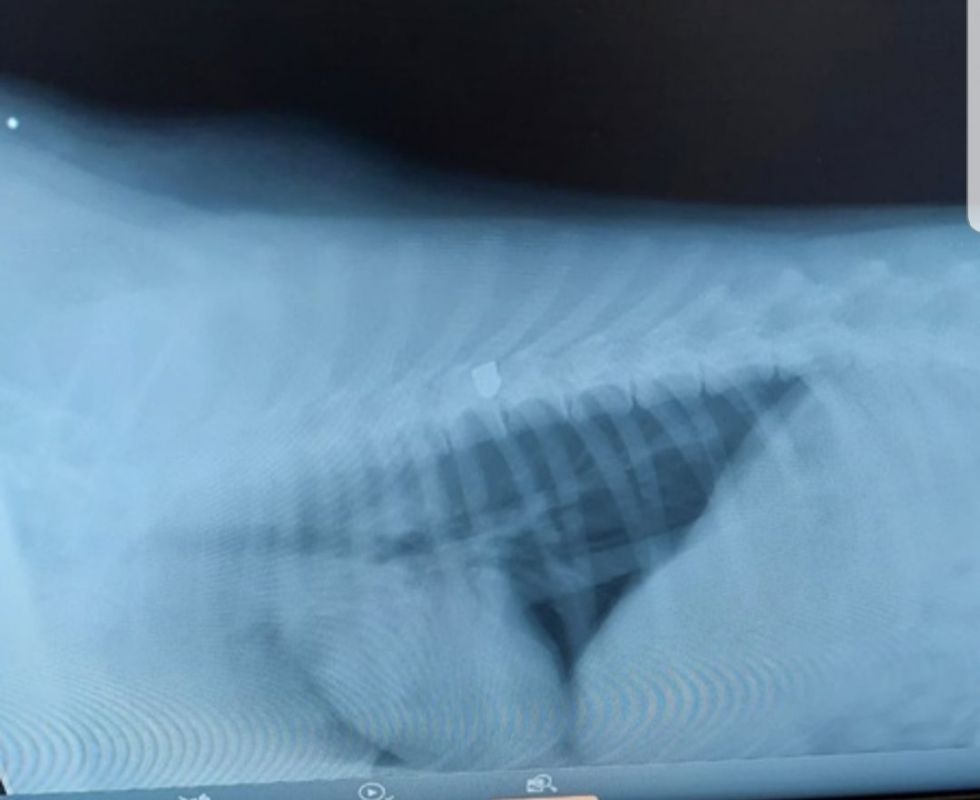

Несколько псов погибло, одной собаке чудом удалось выжить. Неравнодушная горожанка отнесла животное в ветклинику. Там выяснилось, что в позвоночнике четвероногого пострадавшего застряла пуля — из-за этого у собаки отнялись задние лапы.